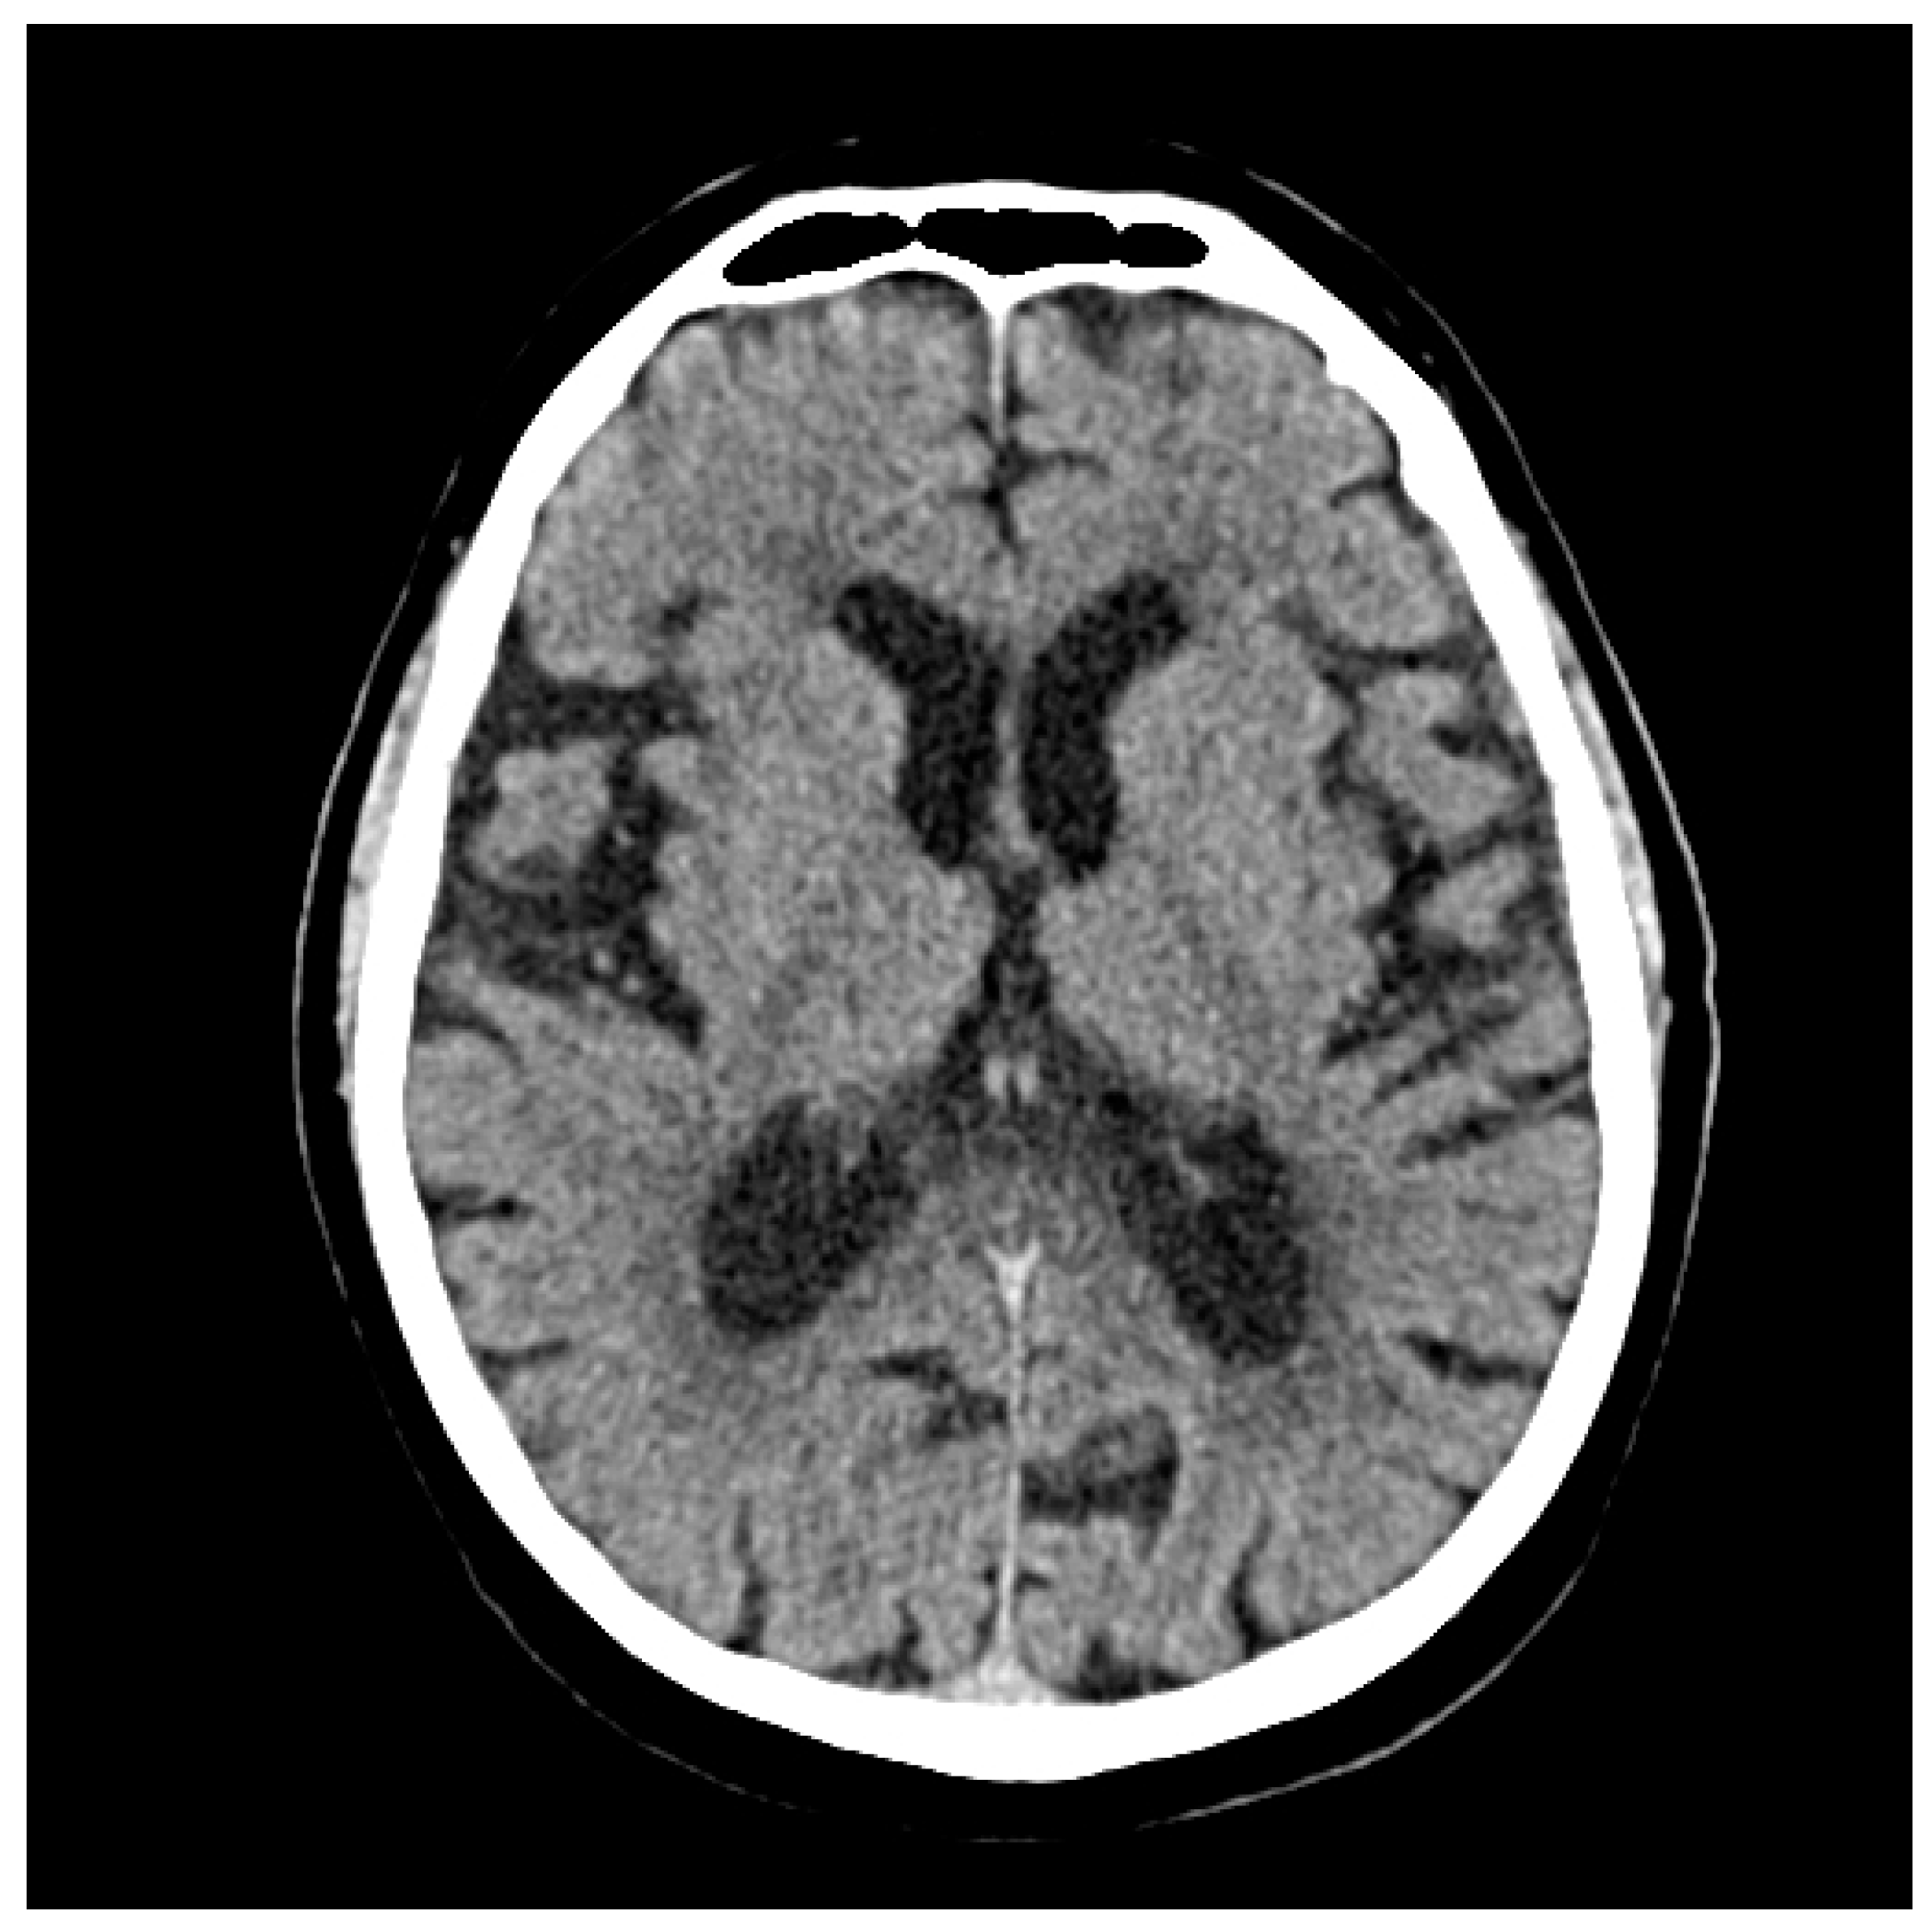

2.1. At the Cerebral Level